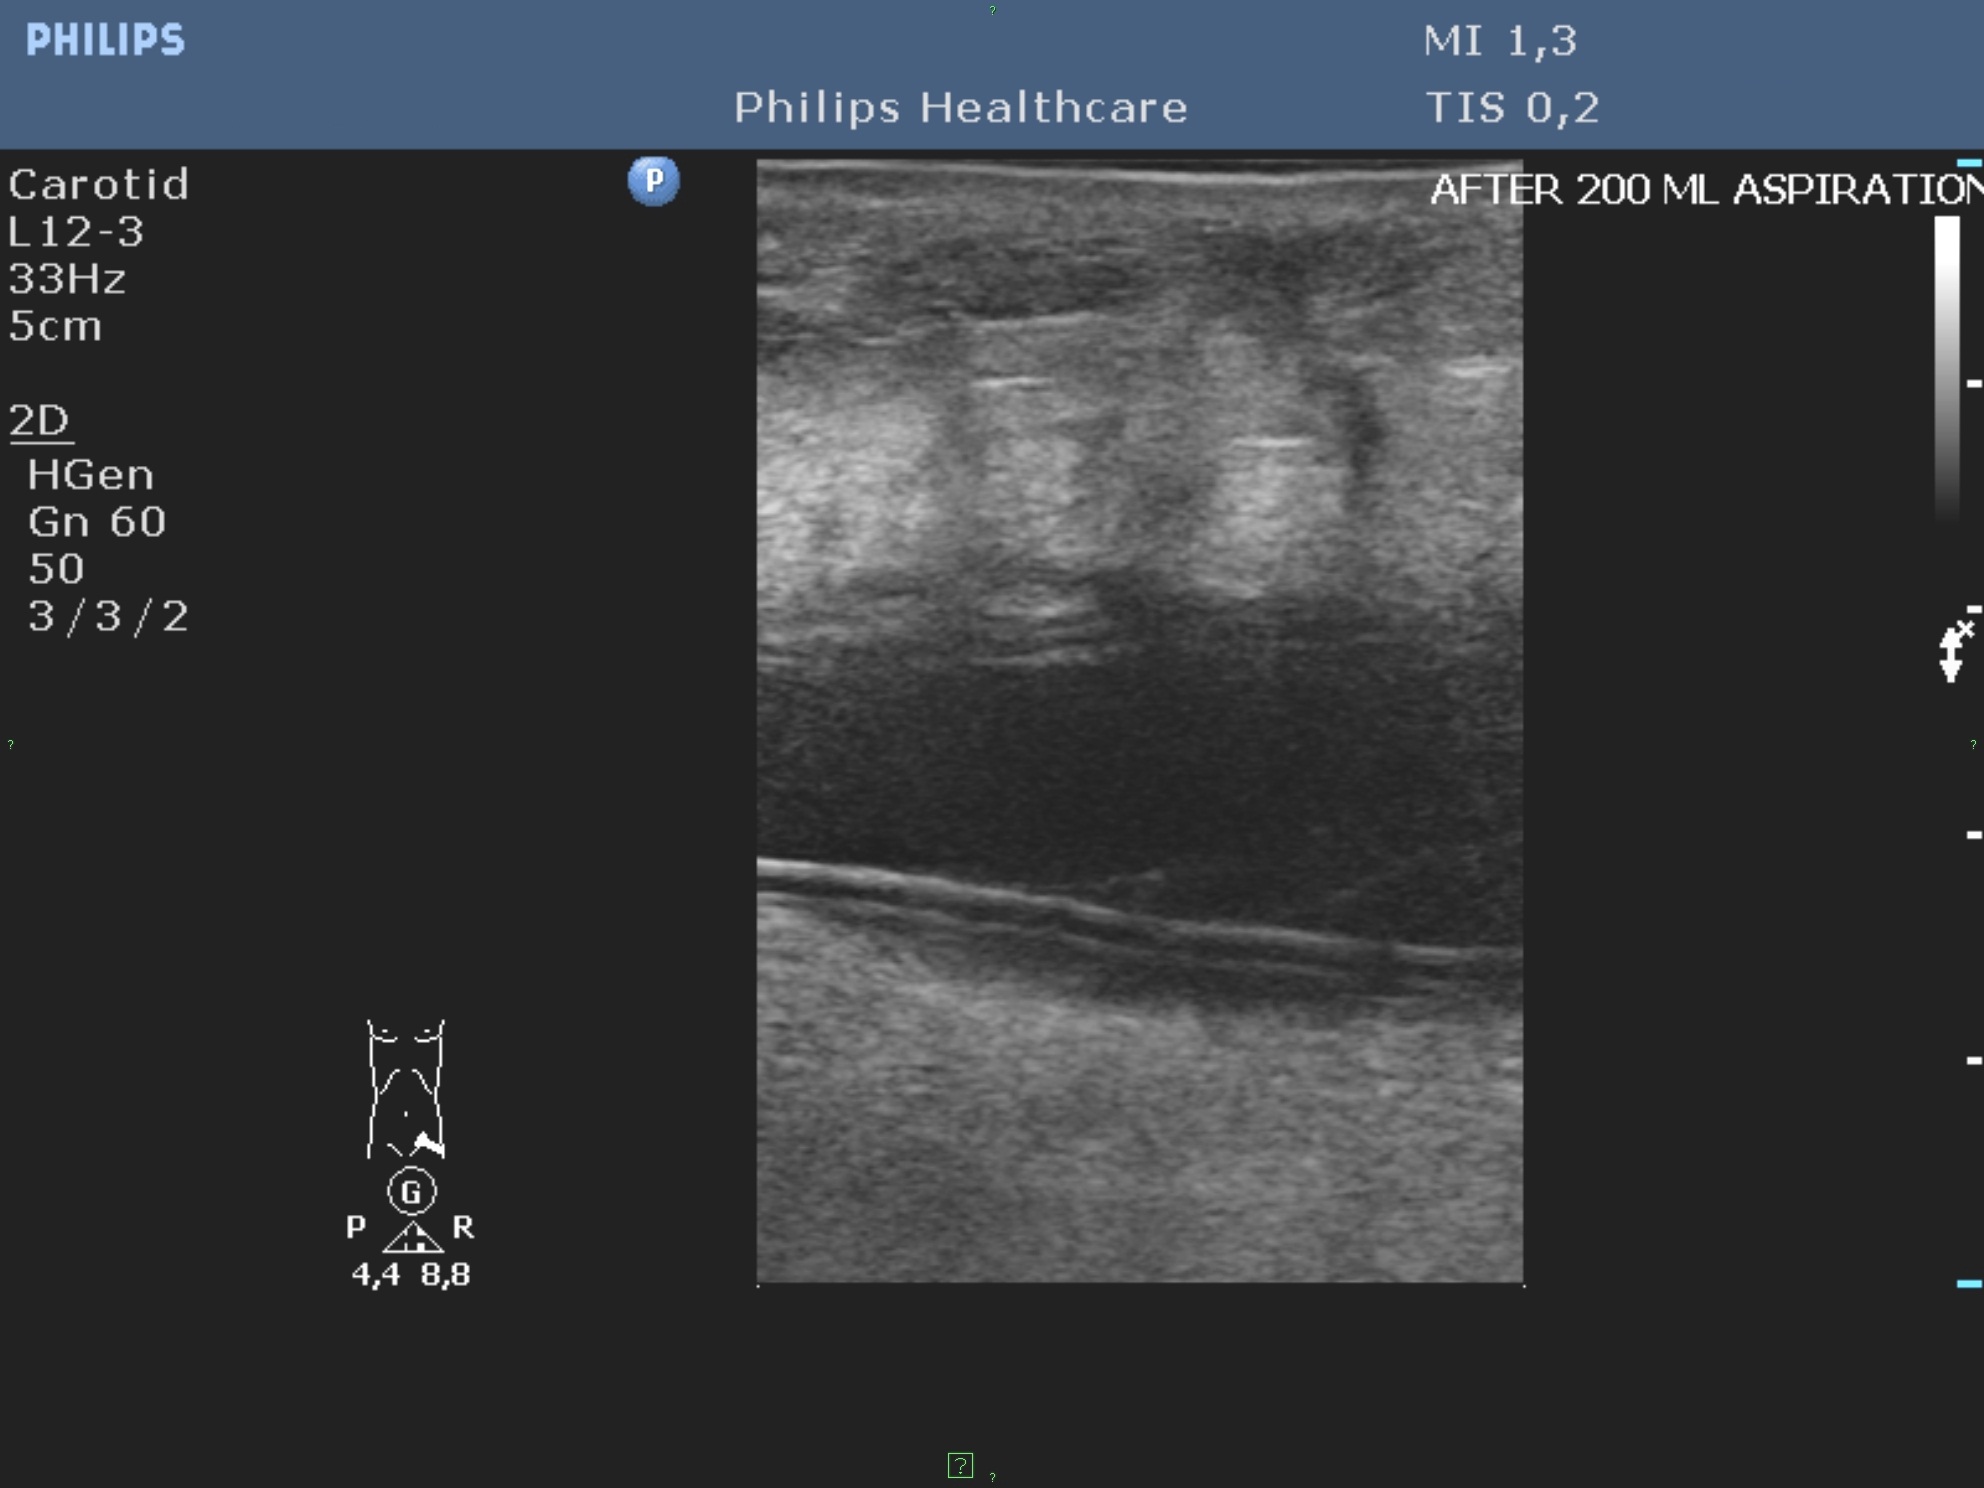

Abscess healing can be accelerated by repeated drainage and lavage of the contents of the abscess. (Figure 11.)

Image

Figure 10. – Hepatic cyst before alcoholic sclerotization, cyst is filled with diluted contrast material.

Figure 11. – US guided hepatic abscess drainage control (day 13, after several rounds of lavage and cleaning of the abscess)

The length of the percutaneous drainage is influenced by the washout of the contents and the reduction of its size.